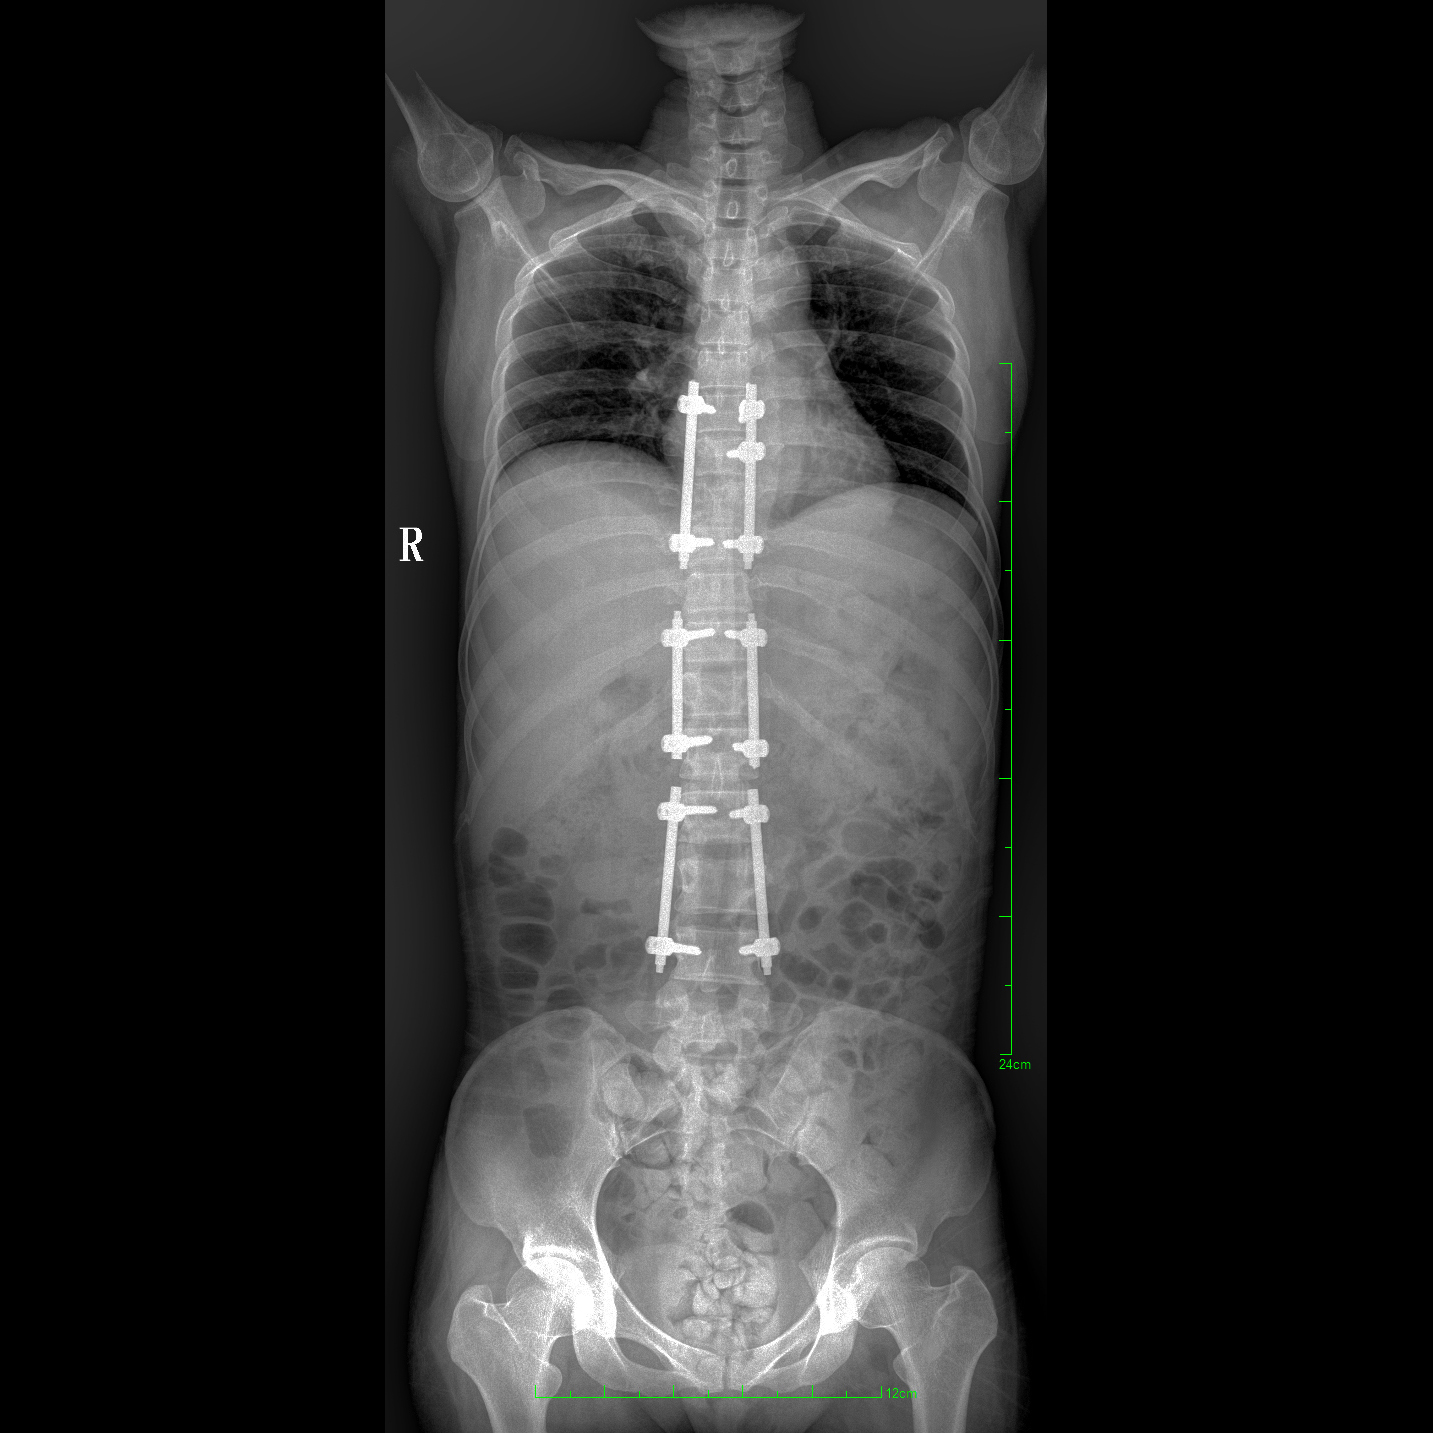

17"*34"有效視野,一次成像不拼接。相較于多張攝影再軟件拼接的DR設備,PLX8600解決了拼接圖像存在密度不均勻,拼接處圖像配準和放大效應等問題,給臨床帶來了大視野影像解決方案,可一次性覆蓋全脊柱或雙下肢影像。

除常規靜態攝影外,PLX8600大平板具備動態透視和點片功能,透視采集功能可支持大視野、多角度的可視化觀察。通過可視化的動態影像,配合點片功能,能夠很好的觀察復雜部位病灶,有效的抓取關鍵幀,降低患者多次攝片的概率。如:全脊柱狀態評估、長骨關節活動度、下肢靜脈造影瓣膜功能評估、消化道功能評估、脊髓造影等更多大視野臨床應用。